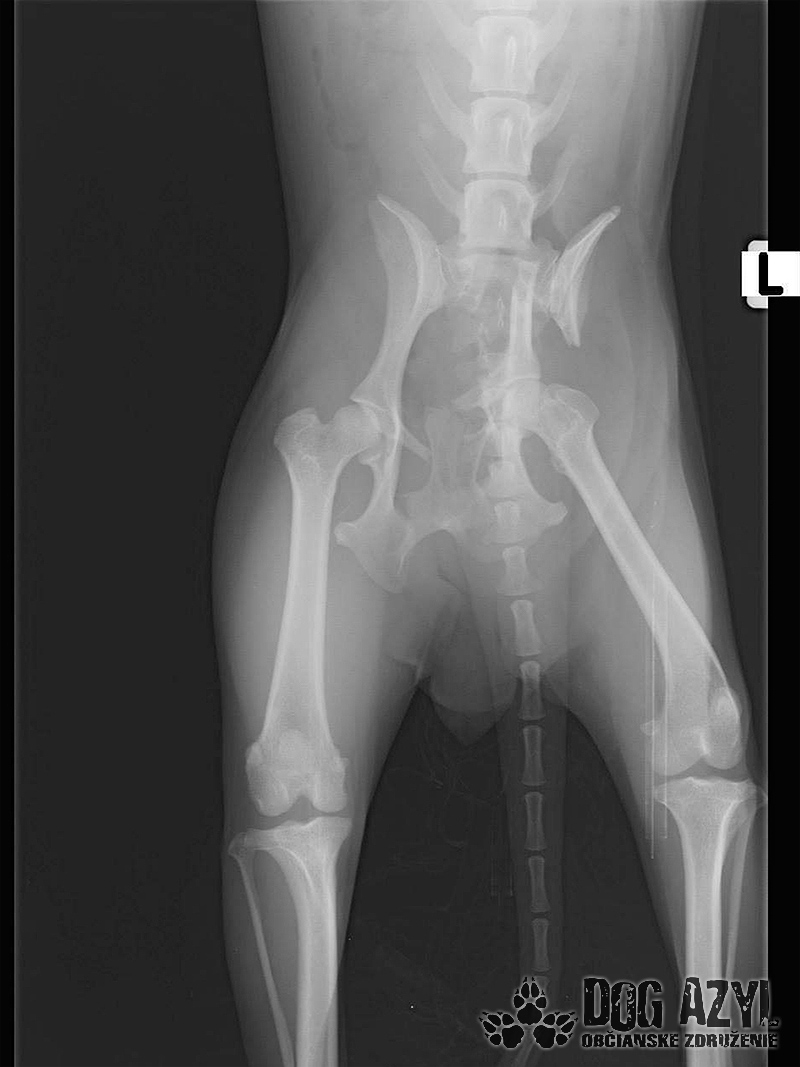

Mia, narodená máj 2015, sa našla zrazená v obci Bodza. Mala obrovské šťastie, že ju nálezkyňa ihneď naložila do auta a utekala s ňou k nášmu veterinárovi. Bola v katastrofálnom stave a mala obrovské bolesti :( Keďže Mia bola čipovaná, hneď sme sa dopátrali aj k majiteľom, ale na druhej strane telefónu nám bolo oznámené, že Miu darovali niekomu ale nemajú kontakt. Tak sme trocha pátrali a vypátrali sme, že Mia bola darovaná "do dobrých rúk" z postele priamo na dvor! Rodina sa tvárila veľmi zodpovedne a láskyplno, ale zrejme nepochopili,že Mia je kastrovaná a už nebude produkovať šteniatka. Po pár neúspešných pokus spáriť ju so samcom putovala do ďalších dobrých rúk" a to k miestnemu alkoholikovi, kde skončila v šope na reťazi a spala na kope hnoja :( Podarilo sa jej nejakým zázrakom ujsť, ale žiaľ skončila pod kolesami auta. Čomu sa vlastne ani nečudujeme, keďže cez tie zlepené chlpy nemala najmenšiu šancu vidieť pred seba. Mia podstúpila veľmi náročnú operáciu panvy, ktorá sa úspešne podarila, ale pri chladnejšom počasí zvykne trocha krívať. Mala tiež zlomený pst na zadnej nohe, ktorý sa zle zrástol a tak jej nechtík rastie trocha krivo a treba ho pravidelne strihať. Vôbec nič jej to však neuberá na kráse a chuti do života :) Mia si hľadá rodinu, ktorá jej vie sľúbiť, že ju nikdy viac neopustí. Je to skôr pokojná fenka, nie je vôbec náročná na pohyb ale na maznanie o to viac :) Veľmi rada sa túli k človeku, je veľmi priateľská a kontaktná. Vôbec jej nevadí spoločnosť iných psíkov ani mačiek ale nepotrebuje ich ku svojej spokojnosti :) Mia je dokonale vhodná do bytu, ale k malým deťom určite nie, má totiž rada svoje súkromie. Ak by sa mala adoptovať k rodinnému domu tak podmienkou je bývanie v dome.